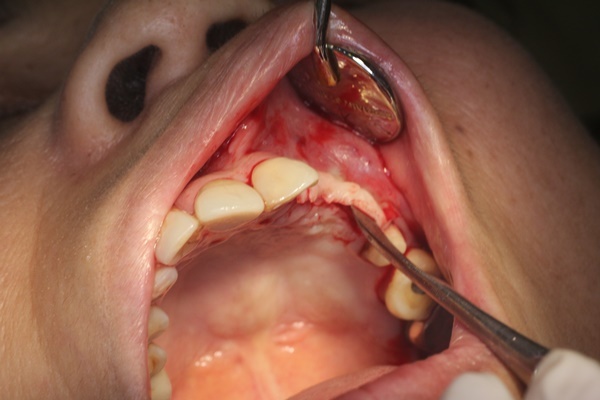

3.植牙設備完善

為患者準備脈膊監視器、血壓計

更設置了【獨立手術室】來控管病毒感染問題

醫師做植牙手術時還需要穿上專用的術衣來做病毒隔離

老婆還偷拍下我植牙手術被蓋上隔離布的樣子

看到照片我當下覺得真得很有趣

另一方面又覺得只是一個小手術

能被這樣重視!!這錢花得很值得!!